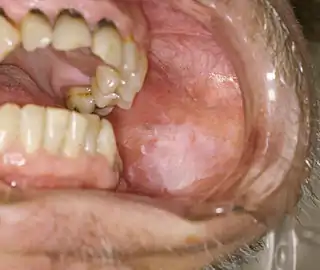

Leucoplasia oral

La leucoplasia oral (del griego leykós, blanco y plasía, proliferación) es una lesión bucal que presenta histológicamente algunas disqueratosis, como: papilomatosis; hiperqueratosis; y acantosis, cuya característica principal es ser una placa blanquecina que normalmente no puede desprenderse por raspado, forma parte del epitelio, y está en crecimiento.

Es blanca porque presenta un engrosamiento epitelial con hiperproducción de queratina. Es una lesión delimitada y asociada a factores que la provocan, sobre todo el tabaco; dejando el consumo de este hábito, puede llegar a remitir. También la lesión puede aparecer en zonas no queratinizadas -suelo bucal, lengua- por lo cual se recomienda hacer siempre biopsia; es complejo saber a simple vista si una lesión es cáncer o leucoplasia.